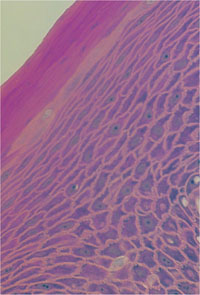

The oral epithelium (Fig 1-6) is a stratified squamous epithelium with several layers, starting with the columnar basal cells. These germinal cells divide to produce cells that move up to the central zone (pentagonal/hexagonal cells within the stratum spinosum and stratum granulosum), which ultimately flatten at the surface and lose their nuclei. The surface cells accumulate an impermeable protein called keratin and upon death they lie along the gingival surface forming a non-nucleated and impermeable keratinised layer (orthokeratinisation). There are over 20 different types of keratin and the keratin profile of epithelial cells characterises where they come from (e.g. gingival epithelium expresses cytokeratin – K1, 2, 5, 6, 10, 12, 16). The basal layer of cells follows a “rollercoaster” course as they travel over connective tissue ridges called “rete ridges” designed to increase the surface area of epithelial-connective tissue contact. The oral gingival epithelium forms a key part of the innate immune response by forming an impermeable physical barrier to bacteria and their products, which is bathed by saliva containing a variety of enzymes (e.g. lysozyme) and imunoglobulins (antibody). As the oral epithelium drops down inside the gingival margin, it becomes SE.

Fig 1-6 Photomicrograph of gingival epithelium from the facial surface demonstrating columnar basal cells (just in view) and pentagonal

cells of the stratum spinosum, with flattened surface cells which have accumulated keratin. Note the absence of nuclei at

the very surface, which is pure keratin and forms the permeability barrier to prevent microbial invasion.

(From Riviere, Lab Manual of Normal Oral Histology. Quintessence: Chicago, 2000)